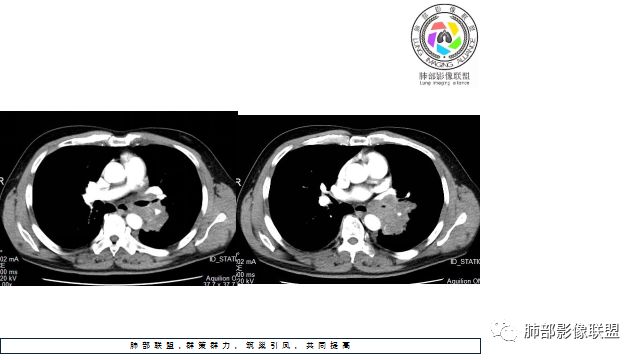

1.左下肺门区巨大肿块,支气管显示不清,轻度阻塞性炎症,没有明显肺不张,提示管腔受压狭窄可能性大于堵塞,这较少见于鳞癌。

2.病灶边缘光滑,未见明显分叶、毛刺,未见明显强化,这符合腺癌影像学特点,却符合神经内分泌癌表现。

3.病灶内密度均匀,轻到中度均匀强化,大病灶未见明显液化坏死区及空洞,不符合鳞癌而符合小细胞肺癌特点。

4.病灶内有肺动脉走形,血管局部受压,未见破坏,病灶乏血供,呈血管包埋或血管造影征;侵袭性力强及破坏力弱、血管漂浮都符合SCLC,所以鳞癌的可能性也不大。

5.左肺门块影或淋巴结肿大,竭力挤兑肺门血管结构,呈冰冻肺门;有时候SCLC可以单独呈现冰冻肺门,而没有没有冰冻纵隔。